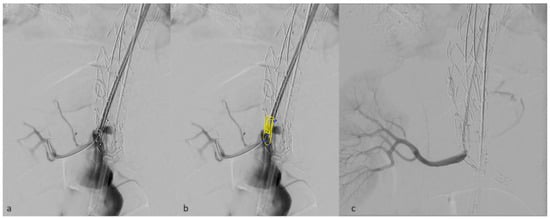

Moreover, the vertical outlets of the inner branches in the E-nside allow for their positioning as fenestrations, minimizing the gap to be bridged outside the graft (Figure 4). This configuration prevents the occurrence of parallel paths between the distal graft’s body and the renal bridging stents, a situation that may lead to stent compression, particularly with the T-branch where outer branch outlets are downward-facing.

Figure 4. Detail of a right renal inner branch outlet used as a fenestration, deployed just in front of the target vessel ostium (a). in panel (b) inner branch characteristics have been added in post-processing. Angiographic result after bridging stent deployment (c).